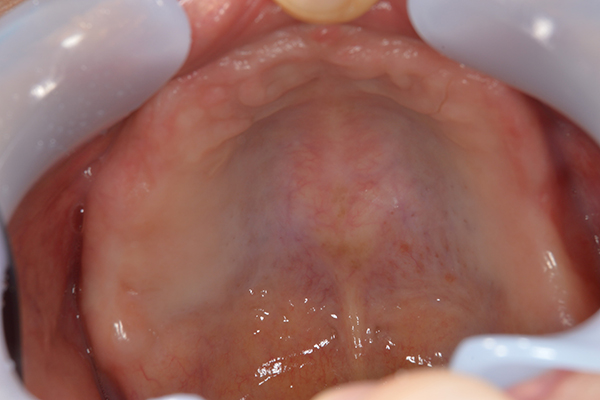

右上と左下の歯がない方です。 上の入れ歯の安定が悪く、作り直したいとのことでいらっしゃいました。 今お使いの上の入れ歯を見てみると、口蓋部分が抜けており、安定性に欠ける構造になっていました。この入れ歯はノンメタルクラスプデンチャーといって、金属のバネを使用しない 入れ歯になります。これは見た目は良いのですが、歯への負担が大きいことと、入れ歯自体がやわらかいため、噛むには不便なことがあります。

お口に入っている状態です。嘔吐反射が強かったため、うわあごの部分をくり抜いて作っています。

嘔吐反射が強く、普通の上顎の入れ歯を入れた時の違和感が強いため、口蓋部をくり抜いてつくっていきました。